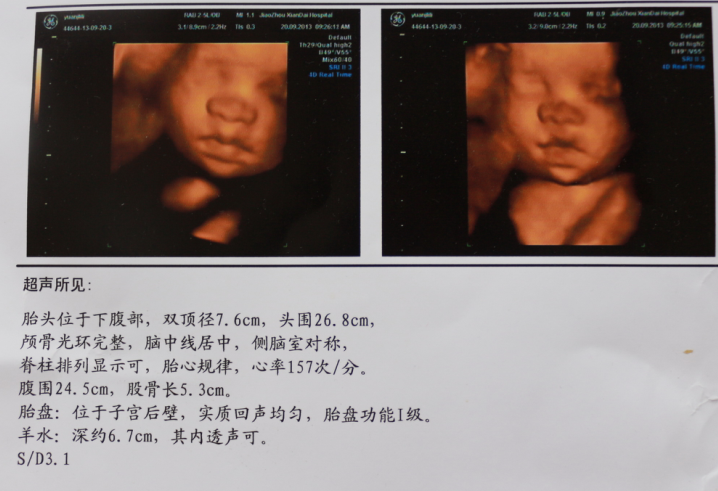

之前的胎心都是140.做彩超的时候孩子 在动是不是就快一点。。胎动很厉害。很有力。